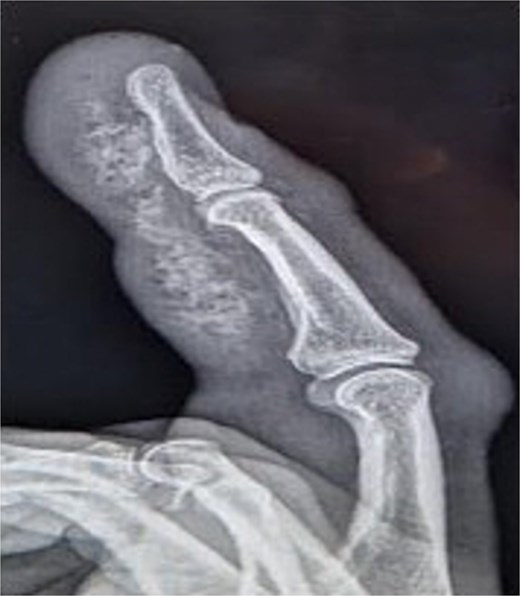

Initial presentation (Fig. 7) with accompanying X-ray (Fig. 8). Final image shows patients digit when he represented 2 months after original insult with a swollen finger and pus exudate (Fig. 9).

X-ray image of patient three showing injected material into surface of his digit, more obvious in the proximal portion.